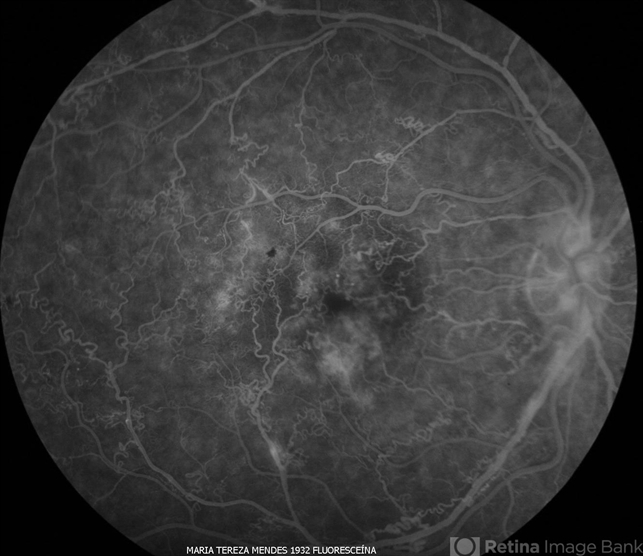

- Idiophatic new vasculitis

- Condition/keywords

- vasculitis, leaky parafoveal capillaries, optic disc leakage, intraretinal hemorrhage

- Idiophatic vasculitis